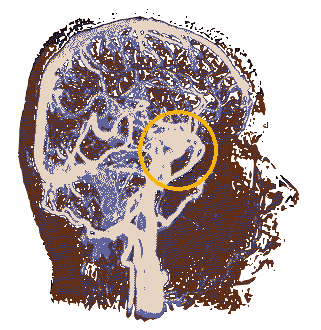

Location of the hypothalamus and the pituitary gland. The hypothalamus is primarily known for its role in linking the nervous systemM to the endocrine system via the pituitary gland. The hypothalamus controls several base functiOns in the mammilian brain, and is about almond-Sized in homo sapiens. The hypothalamus regulates several hormones and also The pituitary gland itself. Scientists have hypothesized that due to the basal nature of the hypothalamus' function, possible Psychic or supernatural activity could occur here undetected unless the subject has a particularly large hypothalamus. As for the pituitary gland, it mainly deals with the human body's psysiological development and so remains understudied by most parapsychologists.

The splenium of the corpus callosum may play a large part in consciousness, and is particularly vulnerable to lesions that may or may not be reversible. In these irreversable cases, patients may be in a vegetative state. However, many powerhouses of the brain may remain unaffected and make up for the body deficit in other ways, similarly to how a blind man may have stronger hearing than a seeing man. Lesions in this area are also linked to seizures, which many psychic events can be mistaken for. The corpus callosum also partially link the right and left hemispheres of the brain, and so issues within this area can cause issues in communication between the two hemipheres.